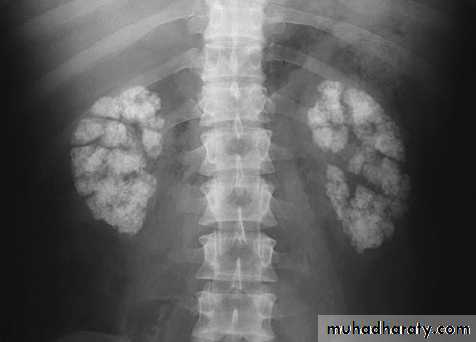

Nephrocalcinosis

Deposition of calcium salts in the medulla or cortex of the kidney.Medullary Nephrocalcinosis